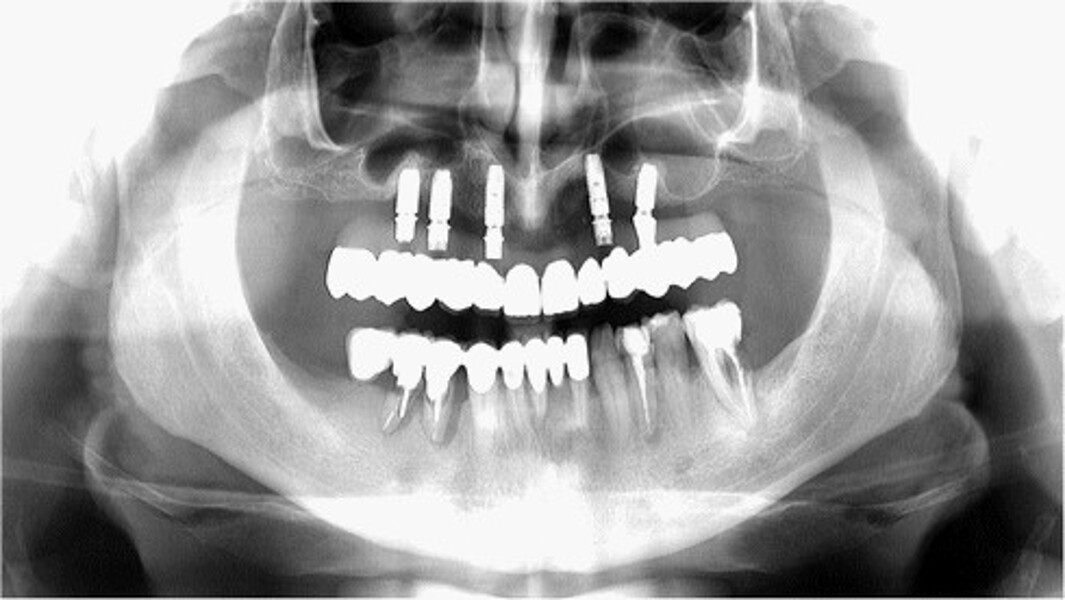

MAGICAL All on FOUR